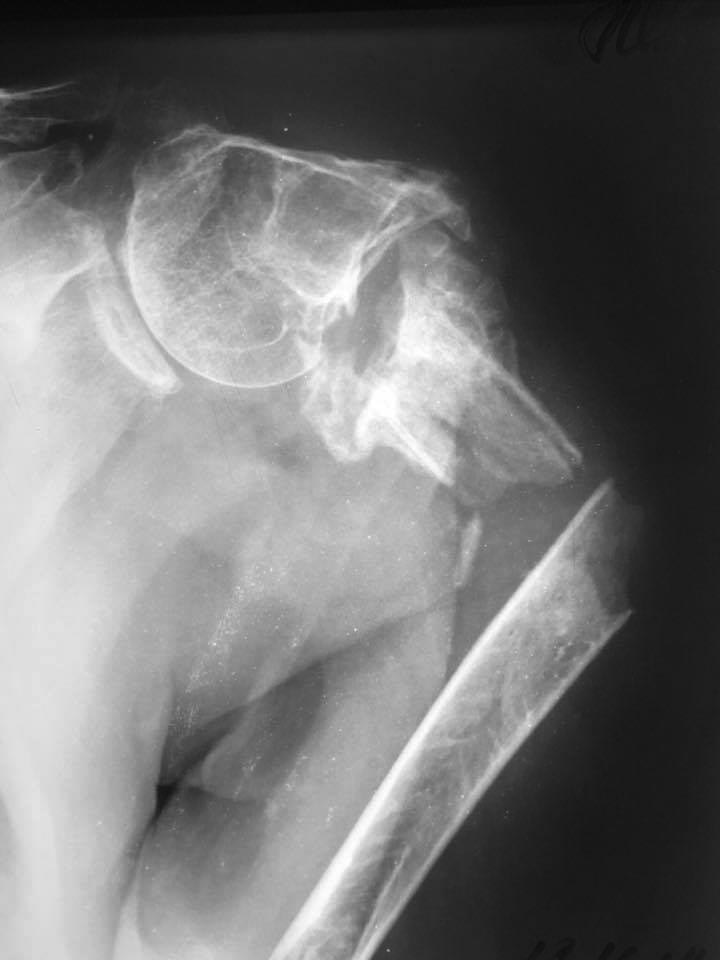

[Ortho] Новый перелом на фоне несращения плеча

Уважаемые коллеги, подскажите ...... в принятии решения? Первая травма 2

года назад. Вторая 2 недели.